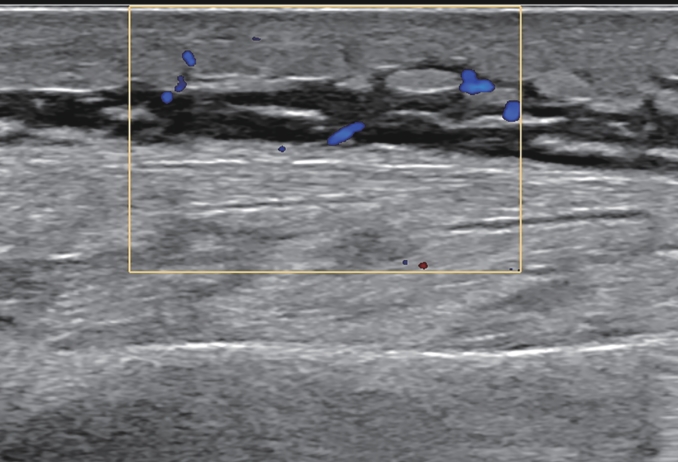

Risk factors for sarcopenia in patients with Wilson’s disease-related liver cirrhosis and their impact on clinical outcomes

Weiqi WANG, Taohua WEI, Nannan QIAN, Wenming YANG, Yulong YANG, Yuqi SONG, Wenjie HAO, Yue YANG, Hu XI, Wei HE

2025, 41(10): 2075-2081. DOI: 10.12449/JCH251018

Abstract:

Objective  To investigate the incidence rate of sarcopenia in patients with Wilson’s disease (WD)-related liver cirrhosis, as well as the risk factors for sarcopenia and their impact on clinical outcomes.  Methods  A total of 140 patients with WD-related liver cirrhosis who were treated in The First Affiliated Hospital of Anhui University of Chinese Medicine from January 2019 to June 2020, and according to the third lumbar skeletal muscle mass index (L3 SMI), the patients were divided into sarcopenia group and non-sarcopenia group. Nutritional risk screening, anthropometric measurements, and blood biochemical tests were performed for the patients to identify the influencing factors for sarcopenia. The patients were followed up for 36 — 48 months, and survival status and complications were compared between the two groups. The independent-samples t test was used for comparison of normally distributed continuous data between two groups, and the chi-square test and the Mann-Whitney U rank sum test were used for comparison of categorical data between two groups. A binary Logistic regression analysis was used to investigate the influencing factors for sarcopenia, and univariate and multivariate Cox regression analyses were used to investigate the risk factors for the prognosis of patients with WD-related liver cirrhosis. The Kaplan-Meier survival curve was plotted, and the Log-rank test was used for comparison between groups.  Results  Among the 140 patients with WD-related liver cirrhosis, 53 (37.9%) developed sarcopenia, with significantly lower body mass index (BMI) and L3 SMI than the patients without sarcopenia (t=10.550 and 3.982, both P<0.001). The multivariate Logistic regression analysis showed that age (odds ratio [OR]=2.243, 95% confidence interval [CI]: 1.196 — 4.208, P=0.012), sex (OR=0.450, 95%CI: 0.232 — 0.872, P=0.018), BMI (OR=0.126, 95%CI: 0.089 — 0.294, P<0.001), and hepatic encephalopathy (OR=8.367, 95%CI: 2.423 — 28.897, P<0.001) were the main influencing factors for sarcopenia in patients with WD-related liver cirrhosis. Compared with the non-sarcopenia group, the sarcopenia group had significantly higher mortality rate (χ2=6.158, P=0.019) and significantly higher incidence rates of infection (χ2=8.008, P=0.040), recurrent abdominal/pleural efflux (χ2=17.742, P<0.001), and hepatic encephalopathy (χ2=4.338, P=0.039). The multivariate Cox regression analysis showed that sarcopenia (hazard ratio [HR]=4.685, P=0.002) and hepatic encephalopathy (HR=19.156, P<0.001) were independent risk factors for death in patients with WD-related liver cirrhosis. The Kaplan-Meier survival curve analysis showed a significant reduction in survival rate in the patients with sarcopenia (P=0.003).  Conclusion  Sarcopenia is one of the manifestations of malnutrition in patients with WD-related liver cirrhosis, which increases the risk of mortality and other complications and has an adverse effect on prognosis. There is an increased risk of sarcopenia in male patients or patients with hepatic encephalopathy, a lower level of BMI or an older age.